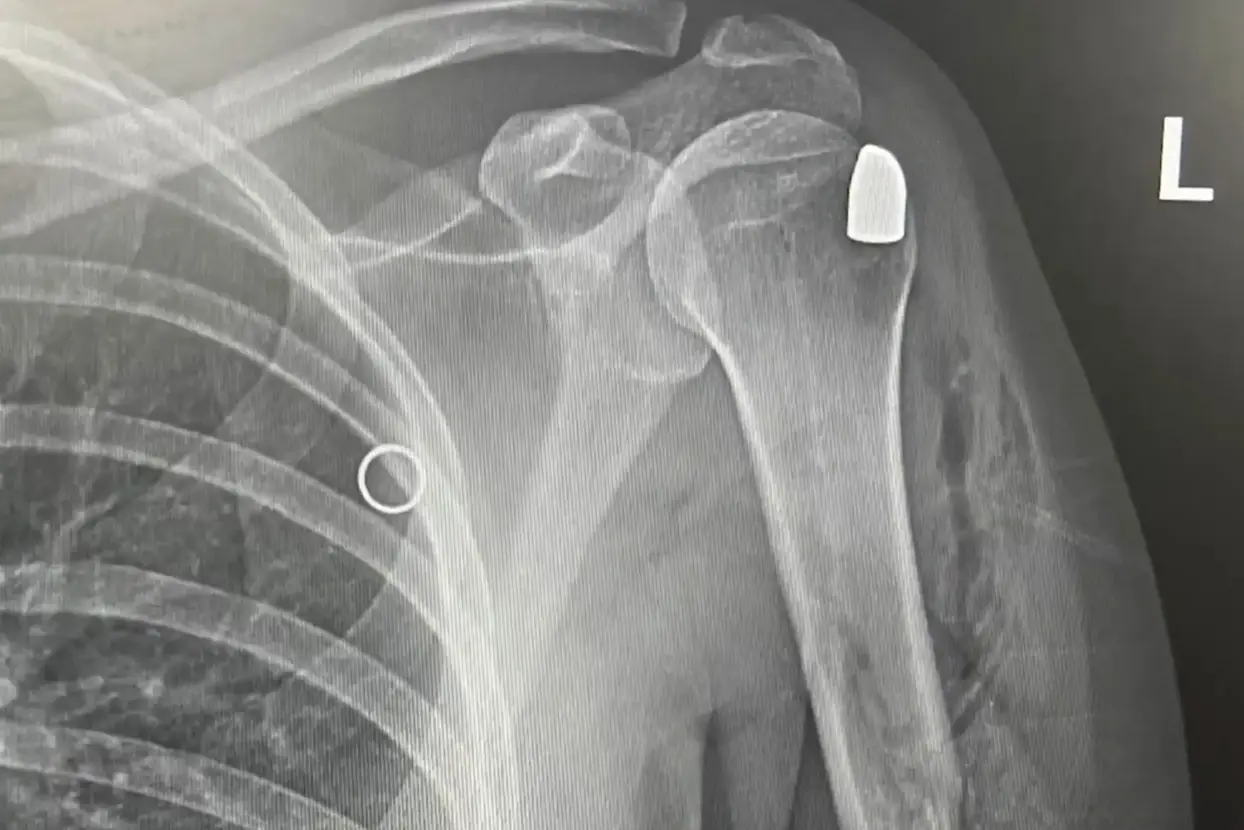

The pregnant mom was subsequently rushed to hospital where doctors found the bullet lodged in her shoulder.

Because of her pregnancy, medical professionals decided to leave the bullet in Heinold's shoulder rather than place her under anesthesia for surgery.